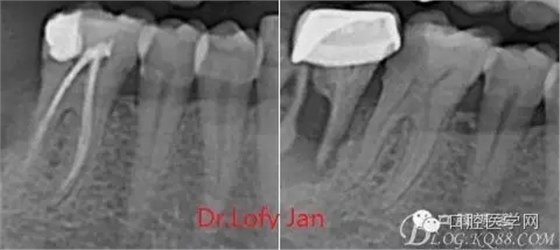

根管治療術(shù)是牙體牙髓疾病治療中最復(fù)雜和最關(guān)鍵的治療項(xiàng)目。根管充填材料抵達(dá)根尖、并能嚴(yán)密堵塞根尖孔,是確保根管治療效果的關(guān)鍵指標(biāo)。為了保證根管充填到位,醫(yī)生需要在術(shù)前照牙片以了解牙根根管的數(shù)量、彎曲程度和長(zhǎng)度,在術(shù)中有時(shí)需要插針照牙片來精確測(cè)量根管長(zhǎng)度,術(shù)后必須照牙片以確定是否根管充填到位,如果欠填或超填,就需要重新充填、重新照牙片確認(rèn),直到根管充填到位。所以,在患者接受根管治療時(shí)有時(shí)會(huì)反復(fù)照牙片。

病例分析:曲面斷層片在x線輔助診斷與檢查中目前大多數(shù)文獻(xiàn)和著作都建議只能作為初診拍片檢查手段,不能作為終末疾病的確診與手術(shù)療效的評(píng)價(jià)指標(biāo),臨床大部分中小型門診都因?yàn)樵O(shè)備不齊全導(dǎo)致信息偏差很大。